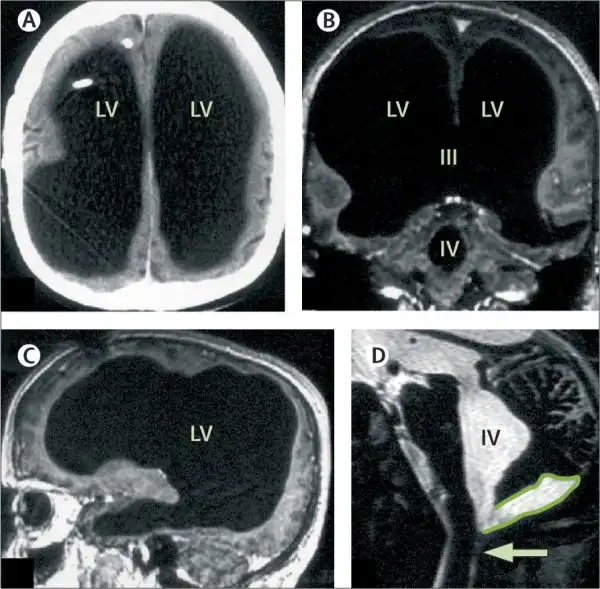

Магнитно-резонансная томограмма пациента с практически отсутствующим мозгом, но ведущим нормальную социальную жизнь.

Французский мужчина, живущий относительно нормальной и здоровой жизнью, несмотря на отсутствие 90% мозга, заставляет учёных пересмотреть теории о биологической сущности сознания.